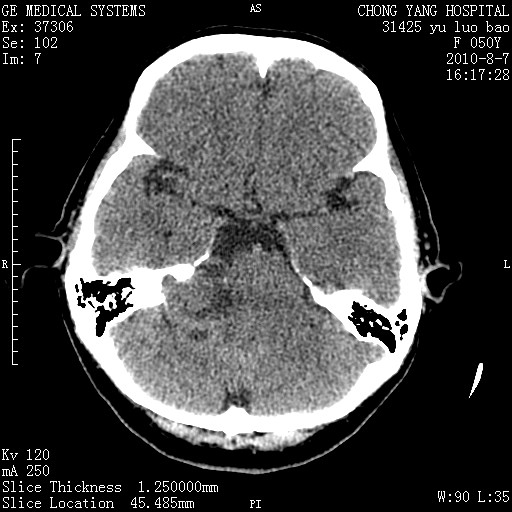

标题: CT28285:听力下降一年,头昏。 [打印本页]

标题: CT28285:听力下降一年,头昏。

右侧桥小脑角去等密度占位,右侧内听道扩大、骨质吸收,考虑:右侧听神经瘤,建议增强检查。

右侧内听道扩大、骨质吸收,中脑受压左移,考虑:右侧听神经瘤,建议增强检查。支持!

右侧桥小脑角区等密度占位,内耳道扩大,听神经瘤